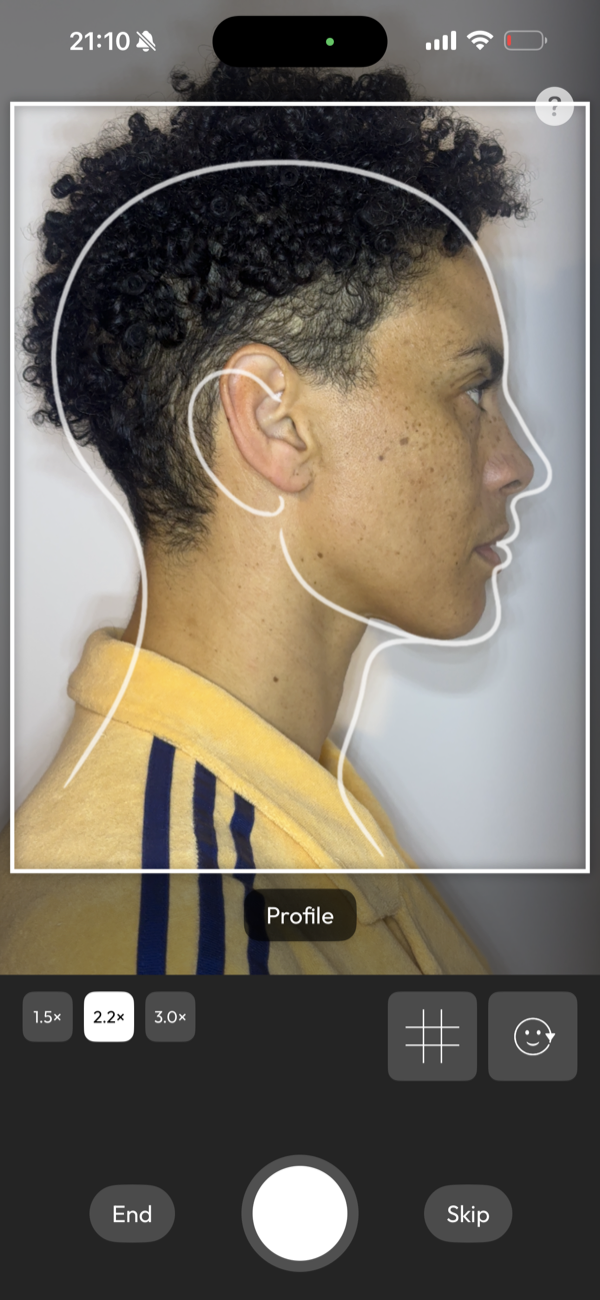

picture perfect images

Capture images with guided precision or import your DSLR work, then transform them into flawless before-and-after cases ready to present and share.

Will phone photos be good enough?

Yes, in most cases.

Modern phone cameras, used with appropriate lighting, are well suited to clinical photography. DentalFolio's guided capture additionally supports consistent framing and orientation. DSLR images can also be imported if preferred.